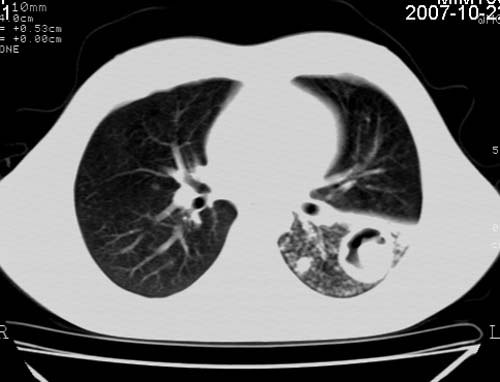

男,21岁,咳嗽、胸闷、乏力伴多汗二十余日、无明显发烧。患者一般情况好,为初三学生。

右肺上叶前段及左肺下叶多形性病变伴厚壁空洞,周边示树芽征.左肺下叶不张改变.

考虑;肺结核,不除外左肺下叶支气管内膜结核.

双肺继发性肺结核伴左侧空洞形成!不除外合并霉菌感染!(双肺多发病灶,左侧病灶形成空洞,并空洞内见壁结节。建议改变体位,观察空洞内结节情况,以便排除霉菌感染!)